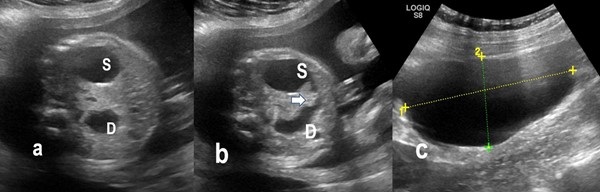

A 33-year-old Indian primigravida with a history of hypothyroidism and Rh isoimmunization came for routine antenatal ultrasonography at 28 weeks and 4 days of gestation. Her triplet or triple test was negative. In her previous ultrasonography, done at 12 weeks, fetal growth parameters were lagging behind LMP [last menstrual period] by 10 days. The present ultrasound showed mild polyhydramnios with an amniotic fluid index of 28, a single umbilical artery, preaxial polydactyly, and fetal growth retardation. The stomach and duodenum were dilated leading to a double bubble sign with a hyperechogenic band surrounding the fetal duodenum (Fig.1). Differential diagnosis of duodenal obstruction either due to annular pancreas, duodenal atresia/stenosis, or malrotation were given. A maternal right ovarian cyst (8.1 x 5.4 cm) was also documented. The fetal amniotic karyotype was normal, 46 XX. Fetal ECHO was also normal. Fetal MRI performed demonstrated dilated stomach and the duodenum giving double bubble sign (Fig.2).

Figure 1

a) Antenatal Ultrasonography at 28 weeks 4 days showing dilated stomach (S) and duodenum (D) giving the Double-bubble sign. b) Hyperechoic band around duodenum (arrow). c) showing the maternal right ovarian cyst